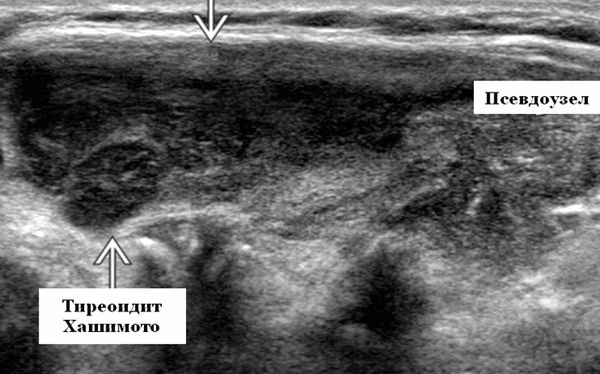

При ультразвуковом исследовании при АИТ обычно отмечается понижение эхогенности железы и появление выраженных диффузных изменений. Переводя на «человеческий» язык, можно сказать, что при аутоиммунном тиреоидите щитовидная железа выглядит на экране УЗИ-аппарата темной и имеет очень неоднородную структуру - в одних местах ткань более светлая, в других - более темная. Нередко врачи ультразвуковой диагностики обнаруживают при болезни Хашимото в ткани щитовидной железы и узлы. Следует отметить, что зачастую эти уплотнения настоящими узлами не являются и представляют собой просто очаги с резко выраженным воспалительным процессом, их еще называют «псевдоузлами». Чаще всего квалифицированный врач ультразвуковой диагностики может отличить псевдоузел при аутоиммунном тиреоидите от узла, однако в некоторых случаях сделать это непросто. Именно поэтому врачи нередко пишут заключение примерно так: «Признаки АИТ. Узлы (псевдоузлы?) щитовидной железы», чтобы подчеркнуть свою неуверенность в оценке характера изменений. При выявлении в ткани щитовидной железы на фоне аутоиммунного тиреоидита образований диаметром 1 см и более пациенту рекомендуется проведение биопсии для уточнения их природы. В ряде случаев после получения результатов исследования становится понятно, что исследованный узел является псевдоузлом на фоне АИТ (ответ цитолога обычно в таких случаях краток: «Аутоиммунный тиреоидит» или «Тиреоидит Хашимото»). Вместе с тем, на фоне аутоиммунного тиреоидита возможно выявление и узлов коллоидного (доброкачественного) строения, и злокачественных новообразований.

- Гипертрофический тиреоидит (с увеличением щитовидной железы) = тиреоидит Хашимото, причём чаще встречается узловая (правильнее сказать «псевдоузловая форма» *), размеры железы могут достигать более 80-100 мл в объёме.

Псевдоузлы при АИТ - это очаги с выраженным воспалительным процессом. - Атрофический тиреоидит (с уменьшением железы менее 4.5 мл в объёме - это сумма объёма обеих долей), который надо дифференцировать с врождённой гипоплазией щитовидной железы